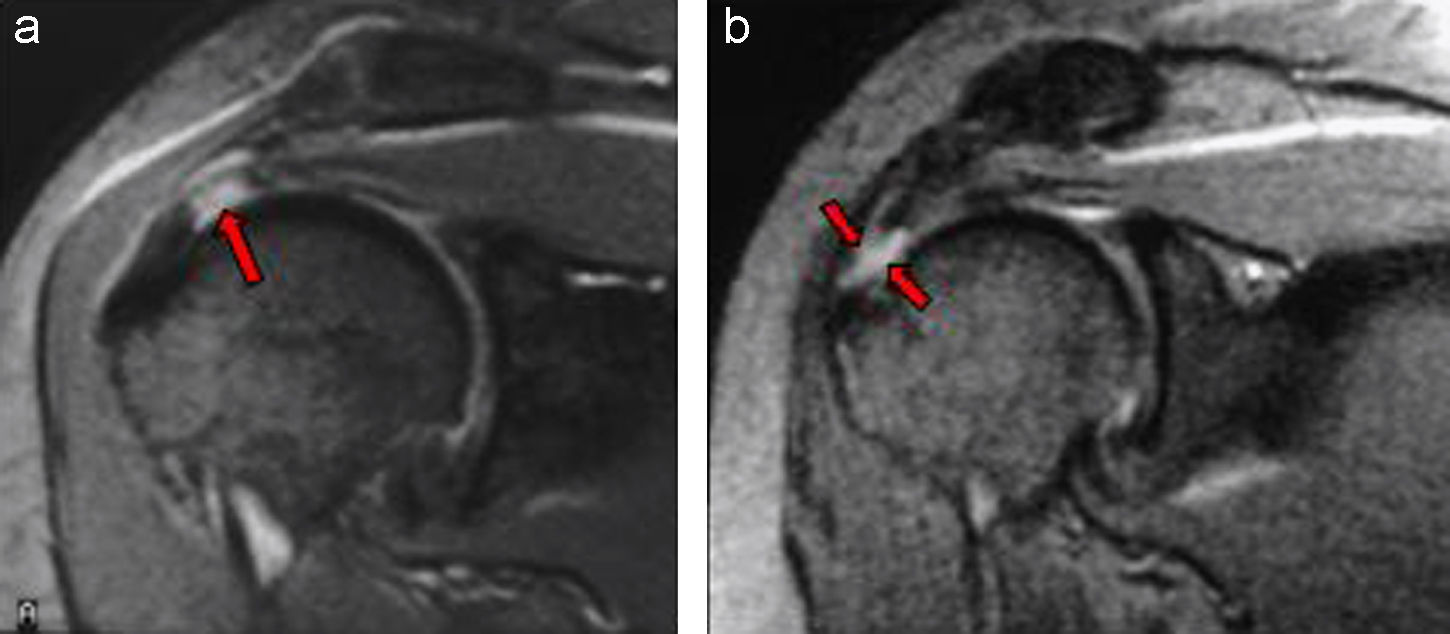

Desalientan la cirugía de decompresión para el hombro doloroso

Una guía de práctica clínica recomienda el manejo no quirúrgico del sindrome de dolor subacromial. British Medical Journal, 6 de febrero de 2016